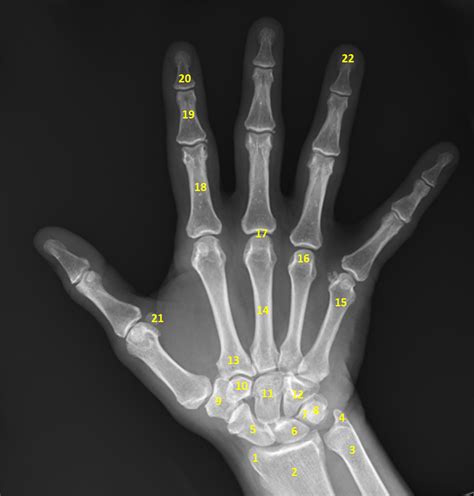

Normal Xray Of Hand . Case study, radiopaedia.org (accessed on 20 aug 2024). Web the hand series consists of posteroanterior, oblique, and lateral projections.

See examples of fractures, dislocations, avulsions and soft tissue injuries with explanations and images. Web benoudina s, normal radiographic anatomy of the hand. Symmetrical joints where the bones do not overlap (except the carpal bones and the base of the metacarpal bones). Although additional radiographs can be taken for specific indications.

Normal Xray Of Hand - Although additional radiographs can be taken for specific indications. Web the hand series consists of posteroanterior, oblique, and lateral projections. See examples of fractures, dislocations, avulsions and soft tissue injuries with explanations and images. Case study, radiopaedia.org (accessed on 20 aug 2024). Symmetrical joints where the bones do not overlap (except the carpal bones and the base of the metacarpal.